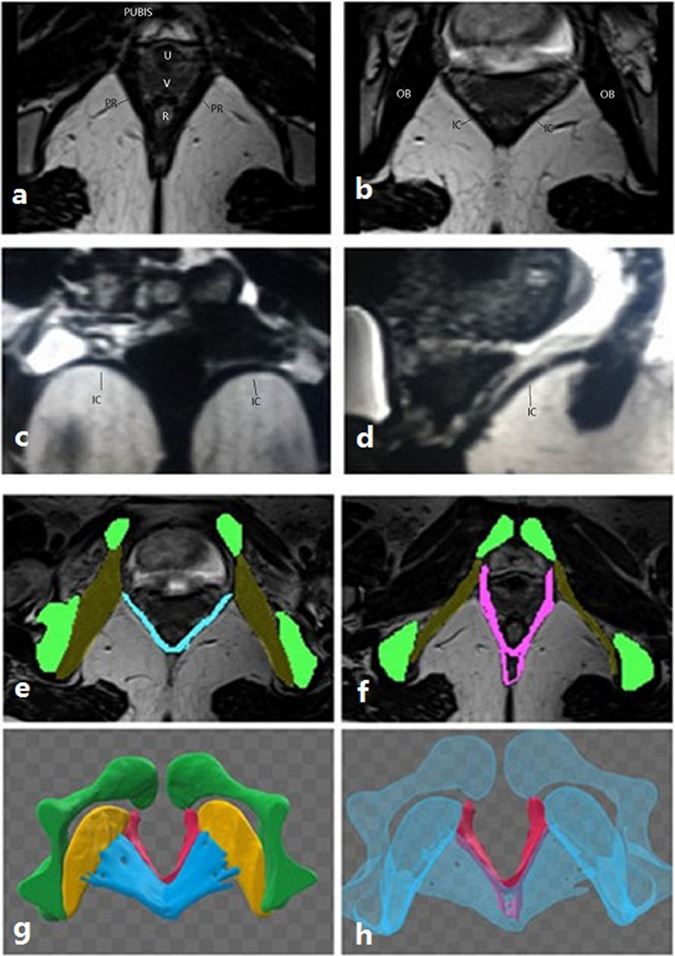

Figure 3.

(a) Shows that the puborectalis originates from the inner surface of the pubic bone and bypasses the rectum to the inner surface of the pubic bone on the other side, like a sling. (b–d) Demonstrate the morphology of the iliococcygeus in the axial, coronal and sagittal planes, respectively. In the coronal plane, it is similar to a wing. In (e,f), the pelvic bone structures are presented in green, the obturator muscle in yellow (showing its attachment to the pelvic medial surface), the iliococcygeus muscle in blue and puborectalis in red. (g,h) Shows the 3D model of the iliococcygeus and puborectalis. In (g), the blue structure is the iliococcygeus, and the red structure is the puborectalis. To better display the puborectalis, which is in the bottom of the iliococcygeus, the iliococcygeus, obturator muscle and bone structure were made transparent as seen on (h). (PR: puborectalis, IC: iliococcygeus, OB: obturator muscle).

The levator ani muscle can be distinguished as the puborectalis and iliococcygeus on MRI. Moreover, the levator ani muscle can be observed in the axial, coronal and sagittal planes (Fig. 3). The puborectalis originates from the inner surface of the pubic bone and runs dorsal to the rectum as a sling (Fig. 3a). The MRI results demonstrated that puborectalis avulsions occurred on the left (n = 4), on the right (n = 4) or bilaterally (n = 3). The iliococcygeus originates from the arcus tendinous levator ani (ATLA), which overlies the obturator internus muscle, bypassing the rectum to the ATLA on the other side (Fig. 3b). In the coronal plane, it was similar to a wing (Fig. 3c). When the wing-like morphology disappeared, damage to the iliococcygeus should be assessed. The sagittal images also showed the orientation of the iliococcygeus muscle (Fig. 3d). On the MRIs, the morphological changes of the iliococcygeus could be well-observed (Fig. 4); it became thin but was still attached to the ATLA (n = 6) (Fig. 4a) or deficient in the middle without avulsion (n = 2) (Fig. 4d), detaching from the ATLA with an obturator muscle injury (n = 2) (Fig. 4b) or without an obturator muscle injury (n = 3) (Fig. 4c).

MRI examination

MRI was performed in one week if puborectalis avulsion was found on at least one side on TUI. The examination was performed using a 3 T scanner (T2M Trio, Siemens, Erlangen, Germany). An external phased-array body coil was employed and was centred at the lower pelvis in supine position. Before examination, all subjects were asked to empty their bladder. Due to the difficulty of holding the Valsalva strain or contract effort during MRI scan, we only analysed static images in this study. Static native T2-weighted turbo spin echo sequences were acquired in the axial plane (TR 1260 ms, TE 130 ms, FOV 400 mm, Slice Thickness 1.00 mm). Section orientation of the axial plane was parallel to the horizontal line—specifically, the levator hiatus—defined as a straight line from the inferior margin of the pubic symphysis to the posterior part of the puborectalis sling24. The morphologies of the puborectalis and iliococcygeus are shown in Fig. 3, and whether there is avulsion in the axial plane, coronal plane and sagittal plane can be defined respectively. The images were analysed by 2 senior radiologists who were blinded to the ultrasound results. Subsequently, the axial plane images were imported into Mimics imaging software to create a 3D model. A 3D model presented the pubic bone, puborectalis, iliococcygeus and internal obturator muscle by tracing the structure outlines on axial images. All 2D images were used to make a 3D model to detect the levator avulsion, including the puborectalis and iliococcygeus avulsion (Fig. 3).